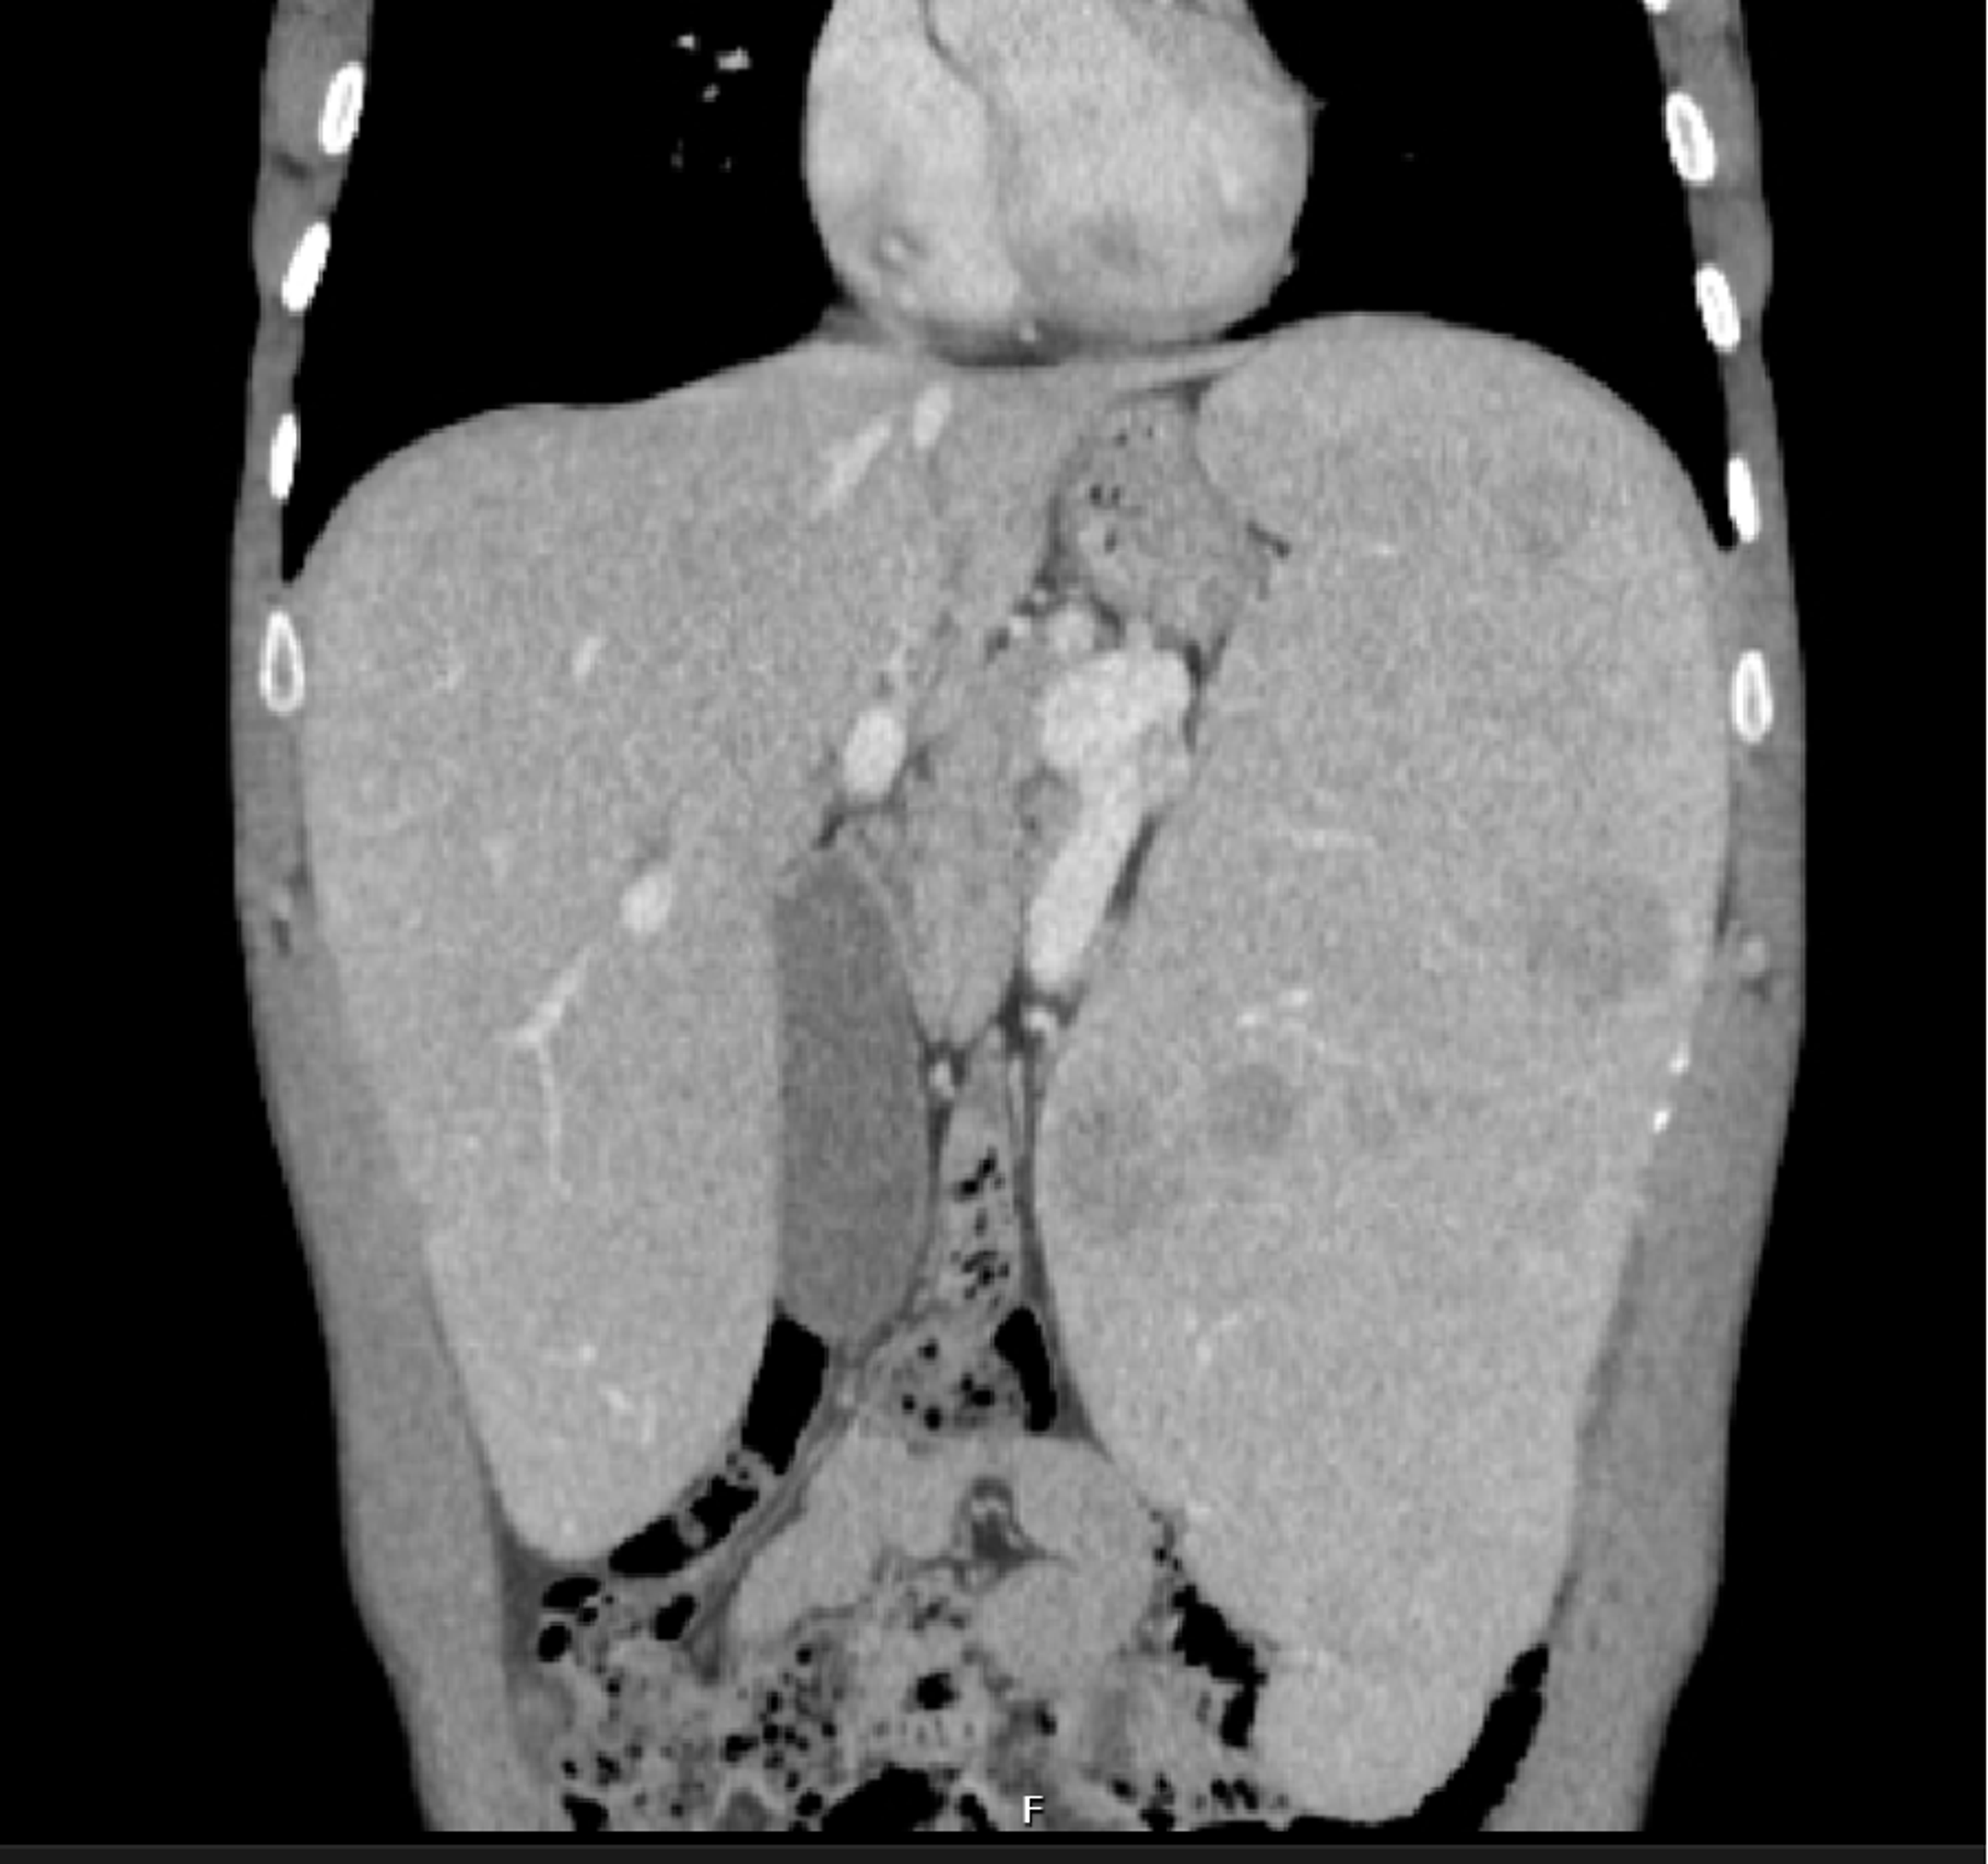

NiemannPick disease type B pulmonary findings (Radiopaedia 43712 Niemann Pick Disease Lung These individuals experience ataxia, dysphonia, dysphagia, liver and lung disease and supranuclear gaze palsy (sngp). This activity reviews the etiology, epidemiology, and. Niemann Pick Disease Lung.

NiemannPick disease type B pulmonary findings (Radiopaedia 43712 Niemann Pick Disease Lung This activity reviews the etiology, epidemiology, and. These individuals experience ataxia, dysphonia, dysphagia, liver and lung disease and supranuclear gaze palsy (sngp). Niemann Pick Disease Lung.